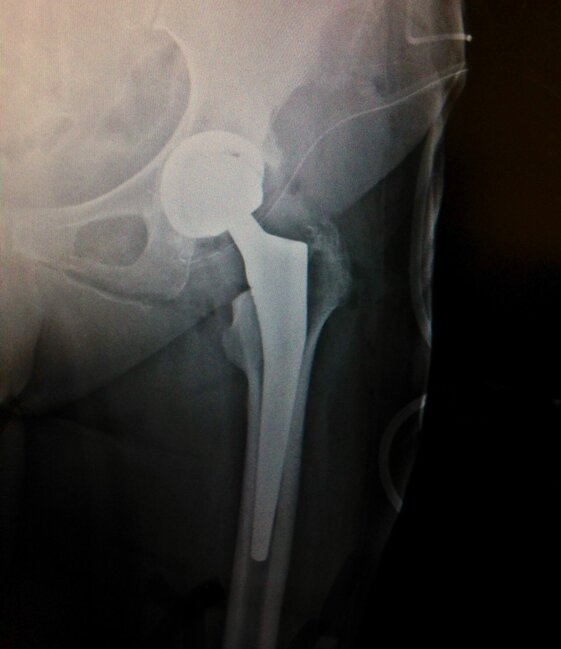

Radiografie post-operatorie in AP di interventi chirurgici di artroprotesi di anca.

In entrambi i casi è stata utilizzata una testa femorale in ceramica ed un inserto in polietilene per l’acetabolo.

A sinistra la protesi utilizzata è a stelo lungo in pz anziano (78 anni), mentre a destra ho utilizzato una protesi con stelo corto e risparmio di osso in quanto il pz era più giovane (65 anni)